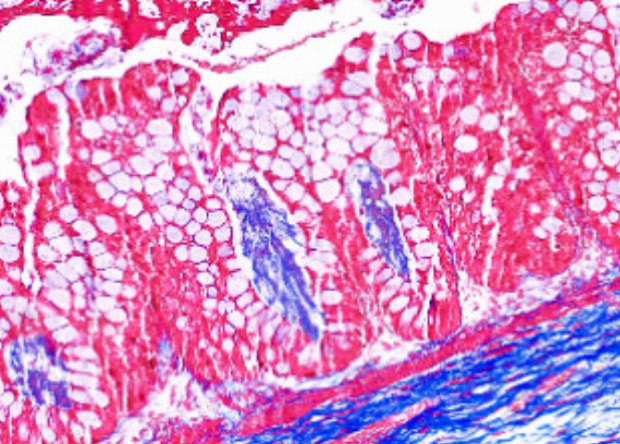

Ученые института Джорджии и Мичиганского университета (США) разработали технологию регенерации дефектов кишечника посредством использования синтетического гидрогеля PEG-4MAL и успешно ее протестировали на грызунах. В ходе эксперимента обработанный специальными средствами гидрогель, заселенный человеческими стволовыми клетками, способствовал получению органоидов, аналогичных человеческому кишечнику.

На втором этапе полученный органоид был трансплантирован мышам и через 12 недель показал увеличение в 10-40 раз, при этом его структура полностью повторяла все ткани кишечника человека.

Успешный опыт подтвердил возможность использования PEG-4MAL для регенерации, поскольку иных методов лечения кишечника не существует в силу особенностей строения органа.